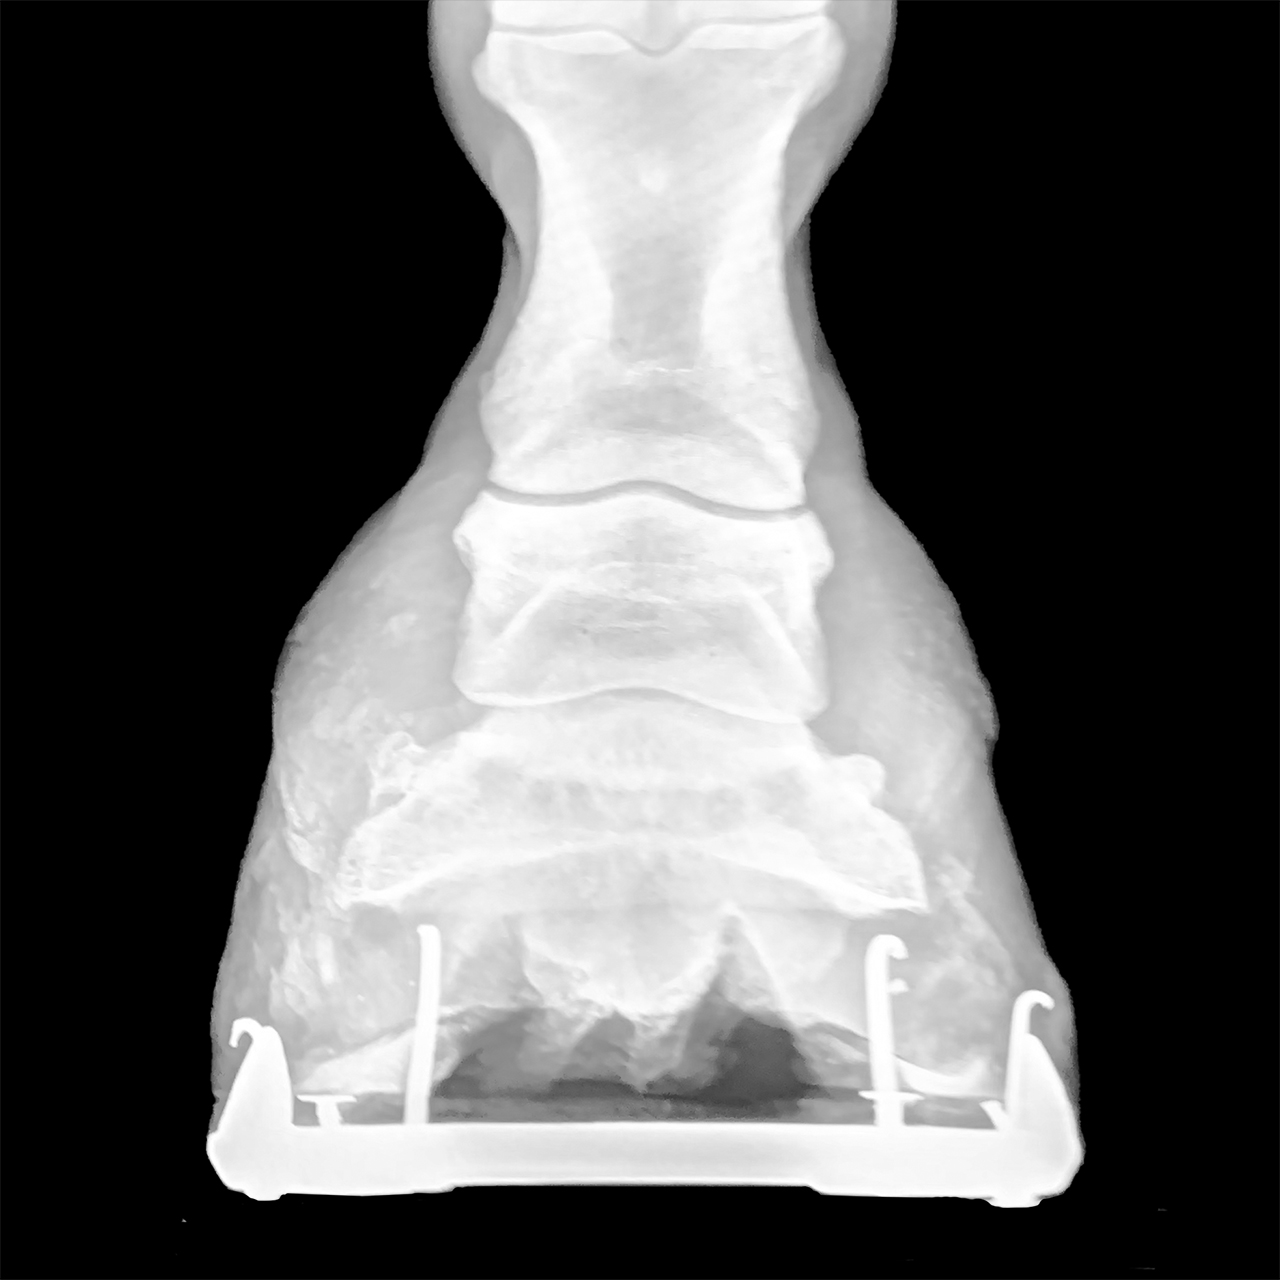

Excessive Distance Between the Coffin Bone and Ground Surface